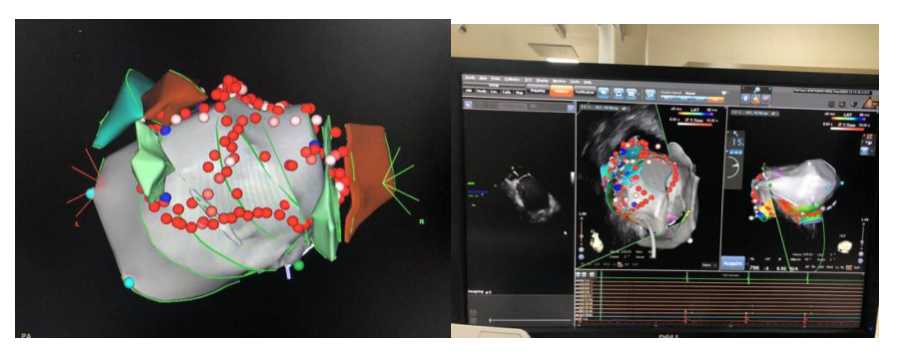

术中通过ICE构建的心脏模型,真实再现心脏结构